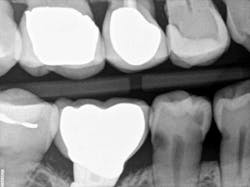

When decay arises on adjacent teeth, dentists must evaluate their treatment options. I have found there is a high degree of difficulty restoring large Class II or interproximal lesions with direct composites, especially when the decay is on premolars. It is much more predictable to restore Class IIs on molars with tight contacts, but it can still be difficult. I have tried full matrix bands and multiple sectional matrix bands, but I can’t create a nice contour with a tight contact. I have even tried traditional composites and bulk fill without great success. See Figures 1 and 2 showing my open contacts with direct composite.

present at DL line angle not seen on radiograph.

food debris in the contact area.